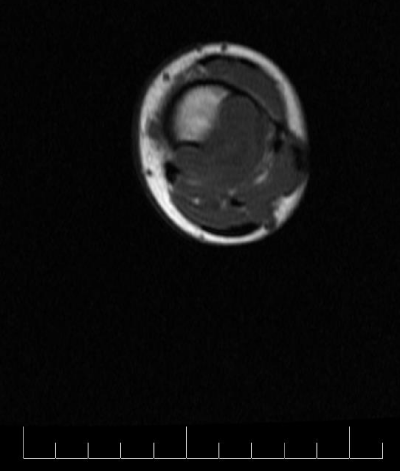

A 10-year-old female presented with left lower leg pain that had progressively increased over the duration of 1 year. On physical examination, tenderness was elicited on palpation of the distal tibia. Routine laboratory testing was normal. X-Ray was performed and revealed a lytic lesion with sclerotic margins in the left lower tibia (Figure 1). MRI was subsequently performed, demonstrating a left lower tibia lesion with low signal intensity on T1 weighted images (Figure 2), and high signal intensity on T2 weighted images (Figure 3). Pathology of the tumor revealed a diagnosis of a CMF. She was treated with curettage and autologous bone grafting (Figure 4). Post op eratively the left leg was immobilized with a plaster cast with restricted weight bearing (Figure 5). Follow up X-ray after 5 years demonstrates no tumor reoccurrence (Figure 6, Figure 7).

Figure 3: MRI sagittal T2 fast spin echo of the left tibia.

MRI demonstrates low signal intensity on T1 weighted images (Figure 2, Figure 11 and Figure 12). T2 weighted images demonstrate high signal intensity (Figure 3, Figure 13). Post gadolinium contrast T1 weighted sagittal view demonstrates diffuse heterogenous enhancement (Figure 14). Post gadolinium contrast T1 weighted axial view demonstrates peripheral nodular enhancement (Figure 15).